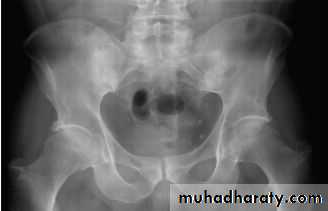

In established AS, radiographs of the sacroiliac joint show irregularity and loss of cortical margins, widening of the joint space and subsequently sclerosis, joint space narrowing and fusion.Lateral thoracolumbar spine Xrays may show anterior ‘squaring’ of vertebrae due to erosion and sclerosis of the anterior corners and periostitis of the waist.

In advanced disease, ossification of the anterior longitudinal ligament and facet joint fusion may also be visible. The combination of these features may result in the typical ‘bamboo’ spine.Erosive changes may be seen in the symphysis pubis, the ischial tuberosities and peripheral joints.